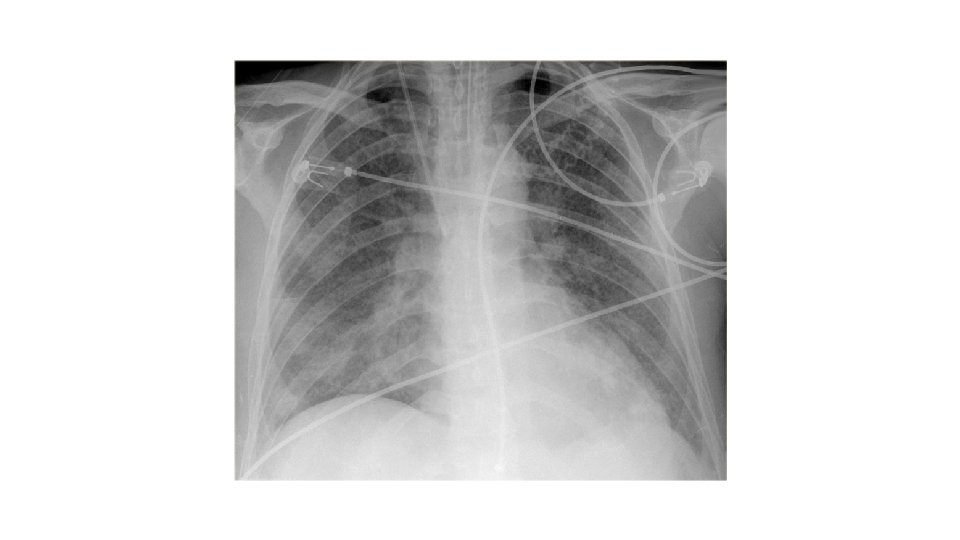

RADIOLOGY • CXR • Sympathetic pleural effusion • Atelectasis • A. R. D. S. • AXR • • • Sentinal loop Colon cutoff sign Duodenal ileus Calcifications Obscured psoas lines • 79% will have radiological signs !!!

Systemic complications • Pulmonary • • • Pleural effusion Atelectasis Mediastinal abscess Pneumonitis Acute respiratory distress syndrome • Cardiovascular • • Hypotension Hypovolemia Sudden death Nonspecific ST-T changes in electrocardiogram simulating myocardial infarction